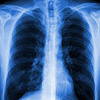

Scientists are developing an inhalable nanosystem to transport TB medicines directly into the lungs.

(Nanowerk News) At the Wits Advanced Drug Delivery Platform (WADDP), postdoctoral researcher Dr Lindokuhle Ngema is developing an inhalable nanosystem to transport TB medicines directly into the lungs, the very place where the bacterium, which causes TB—Mycobacterium tuberculosis—hides and thrives. The nanocarrier (miniature ‘container’ for the medicine) can hold all four standard TB drugs in a single formulation and release them precisely at the infection site. The system is engineered to bypass the liver and bloodstream, reduce drug loss, and increase local concentration in the lungs. “TB is clever,” says Ngema. “It hides in lung pockets where oral drugs can’t reach. Our system is designed to be smarter and to go exactly where it’s needed.”

The standard TB treatment is four key anti-TB drugs: rifampicin, isoniazid, ethambutol and pyrazinamide. They are taken over six months, which creates challenges with adherence. Side effects include nausea, liver damage and neuropathy and may cause patients to stop taking their medicine. TB is thus able to evolve into multidrug-resistant (MDR) and extensively drug-resistant (XDR) forms. The WADDP team believe that inhalation therapy could provide a breakthrough. By delivering medicine directly into the respiratory tract (from the nose and bronchi to the alveoli), inhaled treatment bypasses the body’s barriers and concentrates the drug where it is needed most. “We hope that this could shorten treatment time, improve adherence, and help limit the rise of drug resistance,” explains Dr Ngema.

This is a biocompatible carrier engineered at the molecular level to encapsulate four TB drugs. It is non-toxic and the body doesn’t recognise it as foreign or dangerous. Once inhaled, these nanoparticles travel deep into the lungs and gradually release their payload at the infection site. A key feature is its traceability. Working with the Nuclear Medicine Research Institute (NuMeRI), nuclear imaging will be used to track how the nanoparticles move through the lung in real time. These studies will confirm whether the drug reaches the “hidden” TB pockets that conventional therapy misses. “The beauty of nanoscale science,” says Ngema, “is that you can design a system that responds to the environment inside the body. We can control where and when the drugs are released.” The project was conceptualised at WADDP under Choonara, whose laboratory specialises in targeted nanomedicines and advanced drug delivery systems. Supported by a World Academy of Sciences (TWAS) fellowship, Ngema spent three months in Professor Twan Lemmers lab at the RWTh Aachen University Hospital, Institute for Experimental Molecular Imaging (ExMI) in Germany conducting experiments to optimise the drug release profiles. “We wanted to combine the four main TB drugs in a single inhalable dose, reducing treatment time and making therapy simpler for patients,” Ngema says. “Our early results show that this is possible. Now we’re working to translate it to real-world use.”